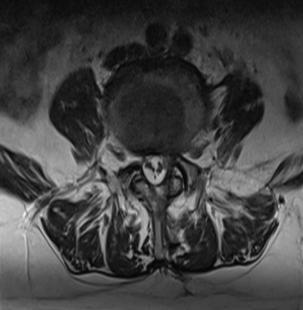

• 不同入路脊柱内镜手术治疗L4/5节段脱垂型腰椎间盘突出症的疗效比较

摘要:目的 观察经椎间孔入路内镜下腰椎间盘切除术(TELD)和经椎板间入路内镜下腰椎间盘摘除术(IELD)治疗L4/5节段脱垂型腰椎间盘突出症(LDH)的临床疗效。方法 回顾性分析2020年11月-2022年11月该院采用脊柱内镜手术治疗的75例L4/5节段脱垂型LDH患者的临床资料。根据手术入路的不同,将患者分为TELD组(53例)和IELD组(22例)。比较两组患者的手术情况和术后疗效。结果 与TELD组比较,IELD组的手术时间明显缩短,术中透视次数明显减少,差异均有统计学意义(P < 0.05);两组患者住院时间和并发症发生率比较,差异均无统计学意义(P > 0.05)。所有患者术后均获得12~19个月的随访。两组患者末次随访时的视觉模拟评分法(VAS)评分和Oswestry功能障碍指数(ODI)明显低于术前,且IELD组明显低于TELD组,差异均有统计学意义(P < 0.05)。按照突出物和神经根的不同位置进一步分析,两组肩上型患者(TELD组10例,IELD组6例)末次随访时的VAS评分和ODI明显低于术前,且IELD组末次随访时的VAS评分明显低于TELD组,差异均有统计学意义(P < 0.05);两组腋下型患者(TELD组8例,IELD组16例)末次随访时的VAS评分和ODI明显低于术前,且IELD组明显低于TELD组,差异均有统计学意义(P < 0.05);35例肩前型患者经TELD术后,末次随访时的VAS评分和ODI明显低于术前,差异有统计学意义(P < 0.05)。按照突出物的不同Lee分区进一步分析,两组Lee Ⅲ区患者(TELD组44例,IELD组10例)末次随访时的VAS评分和ODI明显低于术前,且IELD组的ODI明显低于TELD组,差异均有统计学意义(P < 0.05);两组Lee Ⅳ区患者(TELD组9例,IELD组12例)末次随访时的VAS评分和ODI明显低于术前,且IELD组明显低于TELD组,差异均有统计学意义(P < 0.05)。结论 采用TELD和IELD治疗L4/5节段脱垂型LDH,均可获得较满意的减压效果,但IELD的手术时间相对较短,X线透视次数较少,且对肩上型、腋下型、Lee Ⅲ区和Lee Ⅳ区的减压效果更有优势。